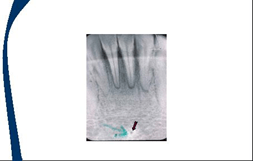

Tuberculo geniano. La imagen circular radiopaca apuntada por las flechas

Foramen lingual. El espacio rdiolucido dentro del tuberculo geniano.

Cresta lingual. La estructura radiopaca en forma de V invertida debajo de las raices de los dientes anteroinferiores.

Borde inferior de la mandibula. La segunda linea radiopaca por debajo de la cresta lingual.